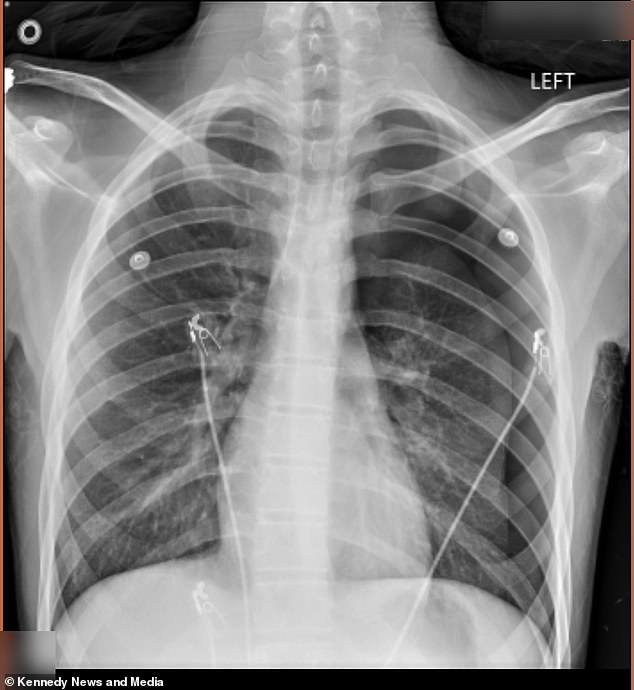

Crystal Vann, a mother from Kentucky, finds herself at the center of a harrowing story that began with her 17-year-old son, Cameron, known as Dodge, vying to fit in with his peers. Two years ago, Dodge picked up vaping as a way to 'look cool' in front of friends, a decision he kept hidden from his mother. His choices came to a painful head in September 2025 when he emerged from the school bus pale and in severe back pain, prompting Vann to rush him to the emergency room. A chest x-ray revealed a devastating truth: 50% of Dodge's left lung had collapsed, a condition known as a pneumothorax, where air accumulates in the chest cavity, compressing the lung and threatening his life.

Doctors acted swiftly, surgically inserting an 18-inch tube into his chest to remove the excess air and allow his lung to re-expand. But the ordeal was far from over. Months later, in January 2026, Dodge called his mother in a panic, breathless and in excruciating pain. 'He called me from school the second time and he said, "I'm hurting, but I don't know if it's my lung or not,"' Vann recalls. 'We went straight to the ER. [The doctors] said he could have died in the lobby.' This time, the damage was worse. His lung had collapsed again, forcing doctors to perform a more invasive procedure called pleurodesis, where they scraped the lining of his lung and stapled air-filled blisters—known as blebs—to the top of his lung to prevent future collapses. 'He went through a lot,' Vann says. 'I thought, "Why him?" I feared he was going to die.'